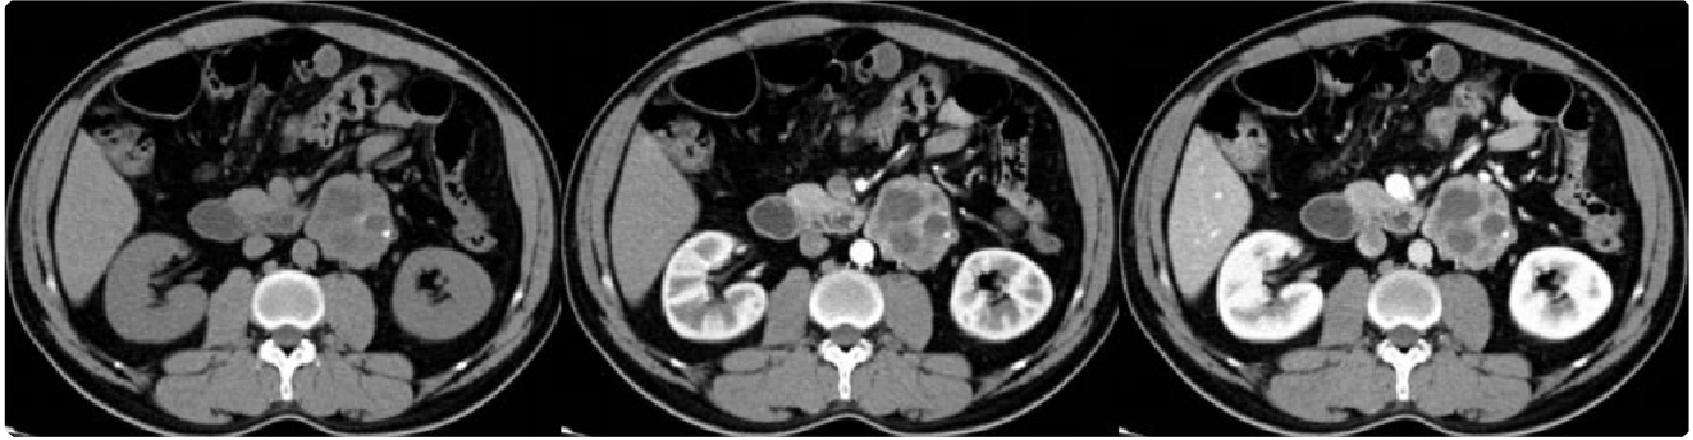

嗜铬细胞瘤病灶通常为3-5cm,小者1cm左右,大者可达15cm。部分形态较规则,病灶内可出血、囊变、坏死、纤维化、脂肪变性、钙化等,约10%嗜铬细胞瘤内可见散在斑点状钙化。约2/3的嗜铬细胞瘤为实性,其余为囊性或囊实性。肿块密度均匀或不均匀,小的肿块密度通常较均匀。

平扫密度值对肾上腺肿瘤诊断具有重要价值,由于肾上腺腺瘤(Adrenal adenoma)常富含脂质,平扫CT值常小于10HU,而大多数嗜铬细胞瘤平扫 CT 值大于10HU,平均CT值约 35.9±9.8HU,少数情况下由于细胞内含有脂质,嗜铬细胞瘤的CT值小于10HU。若瘤内出血,则平扫CT值更高。

嗜铬细胞瘤通常为富血供肿瘤,增强后呈明显强化,囊性区域无强化。病变强化峰值在动脉期,可见肿瘤血管,呈早期、进行性延迟强化。文献报道注射造影剂15min后的延迟期可帮助鉴别腺瘤与其他肿瘤。延迟期腺瘤相对廓清率大于40%或绝对廓清率大于60%,而其他肿瘤如嗜铬细胞瘤相对廓清率小于 40%或绝对廓清率小于60%。但是嗜铬细胞瘤可发生病理上多种变性致影像表现不典型,易误诊为腺瘤或转移瘤。

MRI常表现为 T1WI低信号、T2WI高信号,T2WI也可呈低信号,增强后呈明显强化。同反相位信号变化常用于区分腺瘤与其他肿瘤,但由于嗜铬细胞也可发生脂肪变性,反相位上信号可减低,此时易误诊为腺瘤。